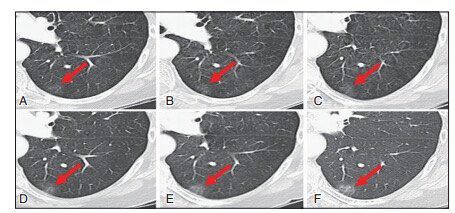

▲图10患者女性,70岁。表现为纯GGN的浸润性腺癌(鳞屑样生长为主)。图A~F为2005-2010年左下肺叶同一病变的CT轴位图像,病灶从最早的微薄的纯GGN逐年呈现大小和密度缓慢递增。最终手术切除证实为鳞屑样增长的浸润性腺癌